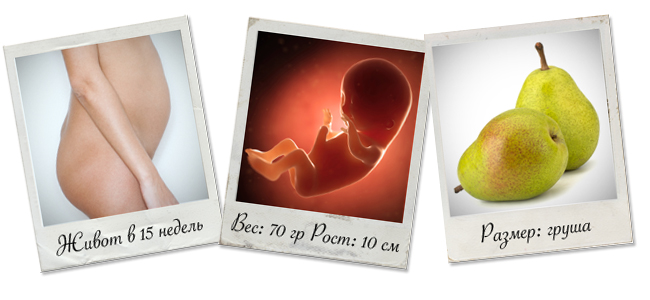

Расположение плода на 15-й неделе беременности: фотографии и иллюстрации